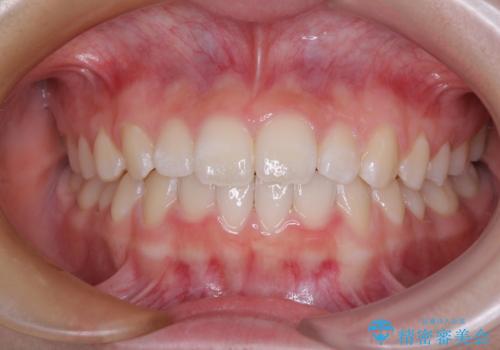

[ 再生治療・歯周外科・小矯正・セラミック補綴 ] 前歯の歯周病治療

担当医 大元洋佑

![[ 再生治療・歯周外科・小矯正・セラミック補綴 ] 前歯の歯周病治療の症例 治療前](https://seimitsushinbi.jp/wp/wp-content/uploads/2022/12/83065c2454a29ed71cf190e15a6106f4-500x350.jpg?v=1671673398)

![[ 再生治療・歯周外科・小矯正・セラミック補綴 ] 前歯の歯周病治療の症例 治療後](https://seimitsushinbi.jp/wp/wp-content/uploads/2022/12/ec16e37ee53325a6f6629b94759f5513-500x350.jpg?v=1671673454)